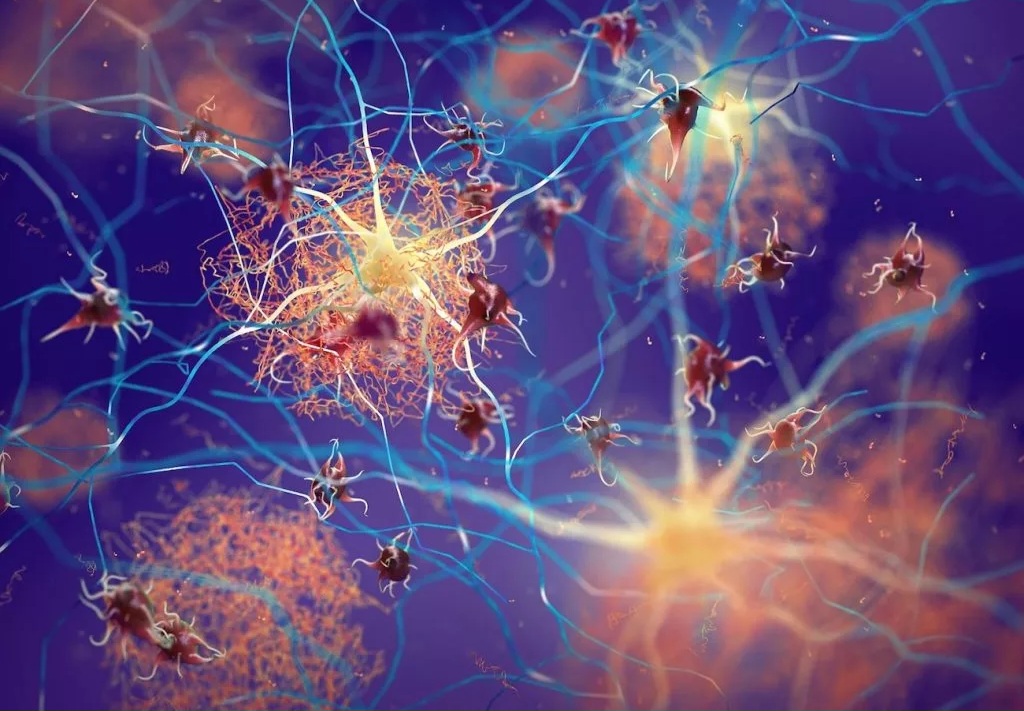

این ساختمان در هلند ساخته شده و با سفر به درون آن میتوان با بازدید از همه بخشها، از کارکرد درست یک بدن سالم آگاه شد و آموزش دید. ارتفاع این ساختمان که از نظر ظاهری پیکر انسانی نشسته است، 35 متر است.

این تصاویر عجیب و بی نظیری كه مشاهده می کنید مربوط به یك ساختمان واقع در كشور هلند است كه شبیه انسان ساخته شده و از تاریخ چهاردهم مارس 2008 برای بازدیدكنندگان فعال بوده است. بطوریکه با سفر به درون آن میتوان از تمامی قسمت ها و کارکرد درست یک بدن انسان سالم اطلاعات لازم را کسب کرد و در این تجربه جدید برای بازدیدكنندگان خصوصا دانشجویان رشته پزشکی این امکان فراهم شده بود تا با قسمتهای داخلی بدن انسان و نحوه فعالیتهای آنها از نزدیك آشنا شوند.

این بنای انسانی که از نظر ظاهری پیکر انسانی نشسته است، در كنار یك ساختمان شیشه ای با ارتفاع 35 متر بنا شده كه در جوار اتوبان A44 آمستردام به هاگو (Hague) قابل مشاهده است. گرچه این تصاویر شاید برای شما دوستان پرشین استار چندان جدید نباشد ولی آنچه مهم است اهمیت آموزش و ایجاد انگیزه برای سهولت در شناخت و درک بهتر ساختمان پیچیده و اسرار آمیز بدن انسان نسبت به نیاز محققین و دانش اندوزانی است که مایلند به گوشه ای از اسرار عظمت خلقت خداوند که همان اشرف مخلوقات است دست یابند.